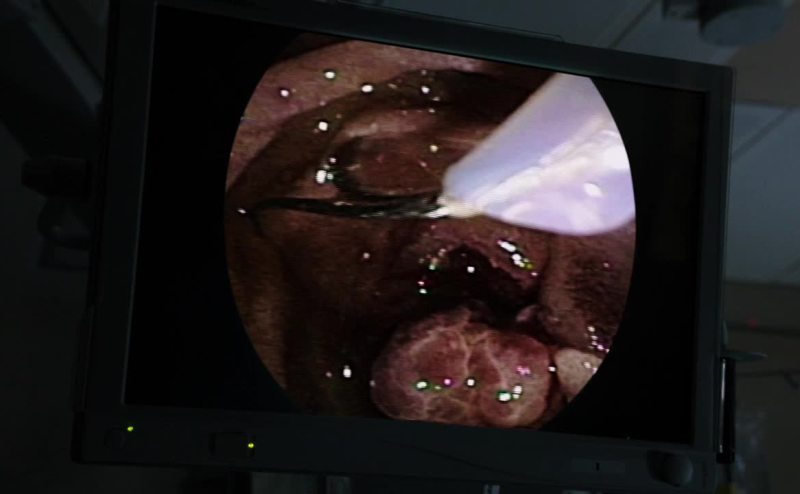

All right, that is the last of the fibroids.

And we're good.

Losing a lot of blood, Doc?

Not more than 100cc's.